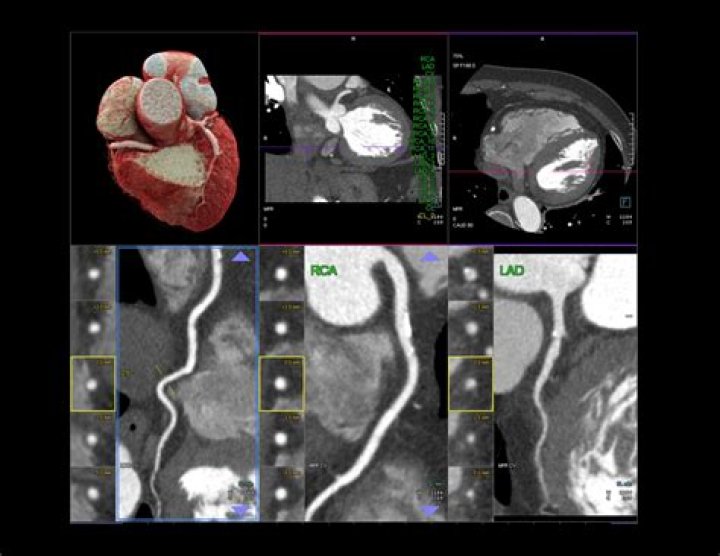

There are several types of CT scans used in the diagnosis of heart disease, including: Calcium-score screening heart scan. Coronary CT angiography (CTA) Total body CT scan.

A CT scan of the heart can show calcium deposits and blockages in the heart arteries. Calcium deposits can narrow the arteries. Sometimes dye is given by IV during this test. The dye helps create detailed pictures of the heart arteries.

A heart computerized tomography (CT) scan, also called a calcium-score screening heart scan, is used to find calcium deposits in plaque of people with heart disease. They're an effective way to spot atherosclerosis before symptoms develop.

It was found that CT angiogram identified 85% of patients with significant stenoses and 90% of patients with CAD accurately. The authors concluded that while CT angiography was not ready to replace conventional angiograms entirely, the more modern procedure was nearly as accurate as the traditional angiogram.